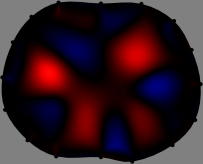

We applied the FER method to experimental data to show its performance. We acquired the boundary geometry and electrode positions as accurate as possible to reduce forward modeling uncertainties[33]. A handheld 3D scanner was used to capture the boundary shape of the thorax and electrode positions (Fig. 1). Then, we set the electrode plane as the horizontal cross-section of the 3D-scanned thorax containing the attached electrodes (Fig. 1). The finite element method was employed to compute the sensitivity matrix 𝕊𝕊\mathbb{S} by discretizing the imaging slice. Here, we used a mesh with 12,001 nodes and 23,320 triangular elements for subject A and a different mesh with 13,146 nodes and 25,610 triangular elements for subject B.

Figs. 3 and 4 compare the performance of the proposed FER method in (20) with the standard regularized least-squares method ((19) when \mathcal{R} is the identity matrix). The regularization parameter of the standard method was heuristically chosen for its best performance, and the parameter of the FER method was set to be one of three different values λ=0.05,0.2,𝜆0.050.2\lambda=0.05,0.2,\infty. The injection current was 1 mARMSRMS{}_{\tiny{\mbox{RMS}}} at 100 kHz, and the frame rate was 9 frames per second. The reference frame at t0subscript𝑡0t_{0} was obtained from the maximum expiration state. The measured data, 𝐕˙(tm)˙𝐕subscript𝑡𝑚\dot{\mathbf{V}}(t_{m}), represent the voltage differences between each time tmsubscript𝑡𝑚t_{m} and t0subscript𝑡0t_{0}. The blue regions, which denote where conductivity decreased by inhaled air, increased during inspiration and decreased during expiration. The FER method with λ=𝜆\lambda=\infty was clearly more robust than the standard method that produced more artifacts originated from the inversion process.

Figure 4: The reconstructed images of the conductivity change of the subject B by the standard regularized least square method and the proposed fidelity-embedded regularization (FER) method for three difference values λ=0.05,0.2,𝜆0.050.2\lambda=0.05,0.2,\infty. Here, the time step is 0.55 seconds (tm+5tm0.55subscript𝑡𝑚5subscript𝑡𝑚0.55t_{m+5}-t_{m}\approx 0.55).